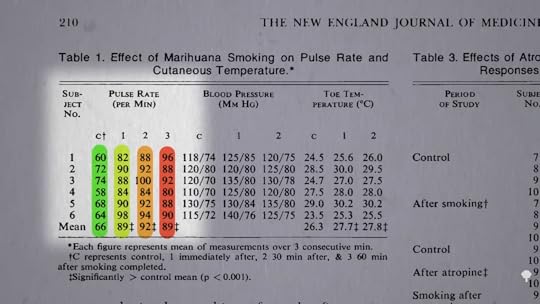

Well, we’ve known since the 1970s that within an hour of smoking a joint, our pulse rate goes up about 35 percent, as you can see below and at 3:20 in my video. Smoking a single joint also increases blood pressure, as well as carbon monoxide levels in the blood of angina patients, and it cuts their ability to exercise nearly in half. Now is that just because they’re breathing in smoke of any kind? No, smoking a placebo joint—that is, a marijuana joint from which the THC has been removed—only cuts down exercise capacity by about 9 percent. In contrast, after smoking an actual cannabis joint, the time the study participants could exercise before experiencing chest pain was cut by 48 percent. So, it does seem to be a specific drug effect. Is it as bad as tobacco? We found that out a year later.